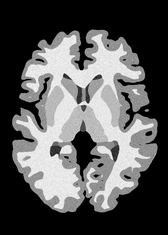

4.2 Registration to a 100 micron ex-vivo brain MRI volume

To showcase the efficacy of our method on real large scale images, we register a 250 in-vivo MRI image (Lüsebrink et al., 2017) to a 100 ex-vivo FLASH human brain volume (Edlow et al., 2019). This represents an inverse problem with more than 11.2B optimizable parameters (compared to 20M for clinical datasets), or 44.8GB of GPU memory. The entire problem does not fit on most GPUs, necessitating distributed multimodal registration. We optimize a composite transform - affine followed by a diffeomorphic mapping; details can be found in Section E.1. Multimodal deformable registration took 58 seconds on 8 NVIDIA A6000 GPUs, which is unprecedented at this resolution. Fig. 6 shows qualitative results, highlighting the ability to register highly detailed structures such as cerebellar white matter; these structures are not visible at macroscopic scales. The resultant advantages of performing registration at this scale can allow researchers to characterize the neuroanatomy at microscopic resolutions and allow morphometric analysis of cortical layers and subcortical nuclei among other structures.